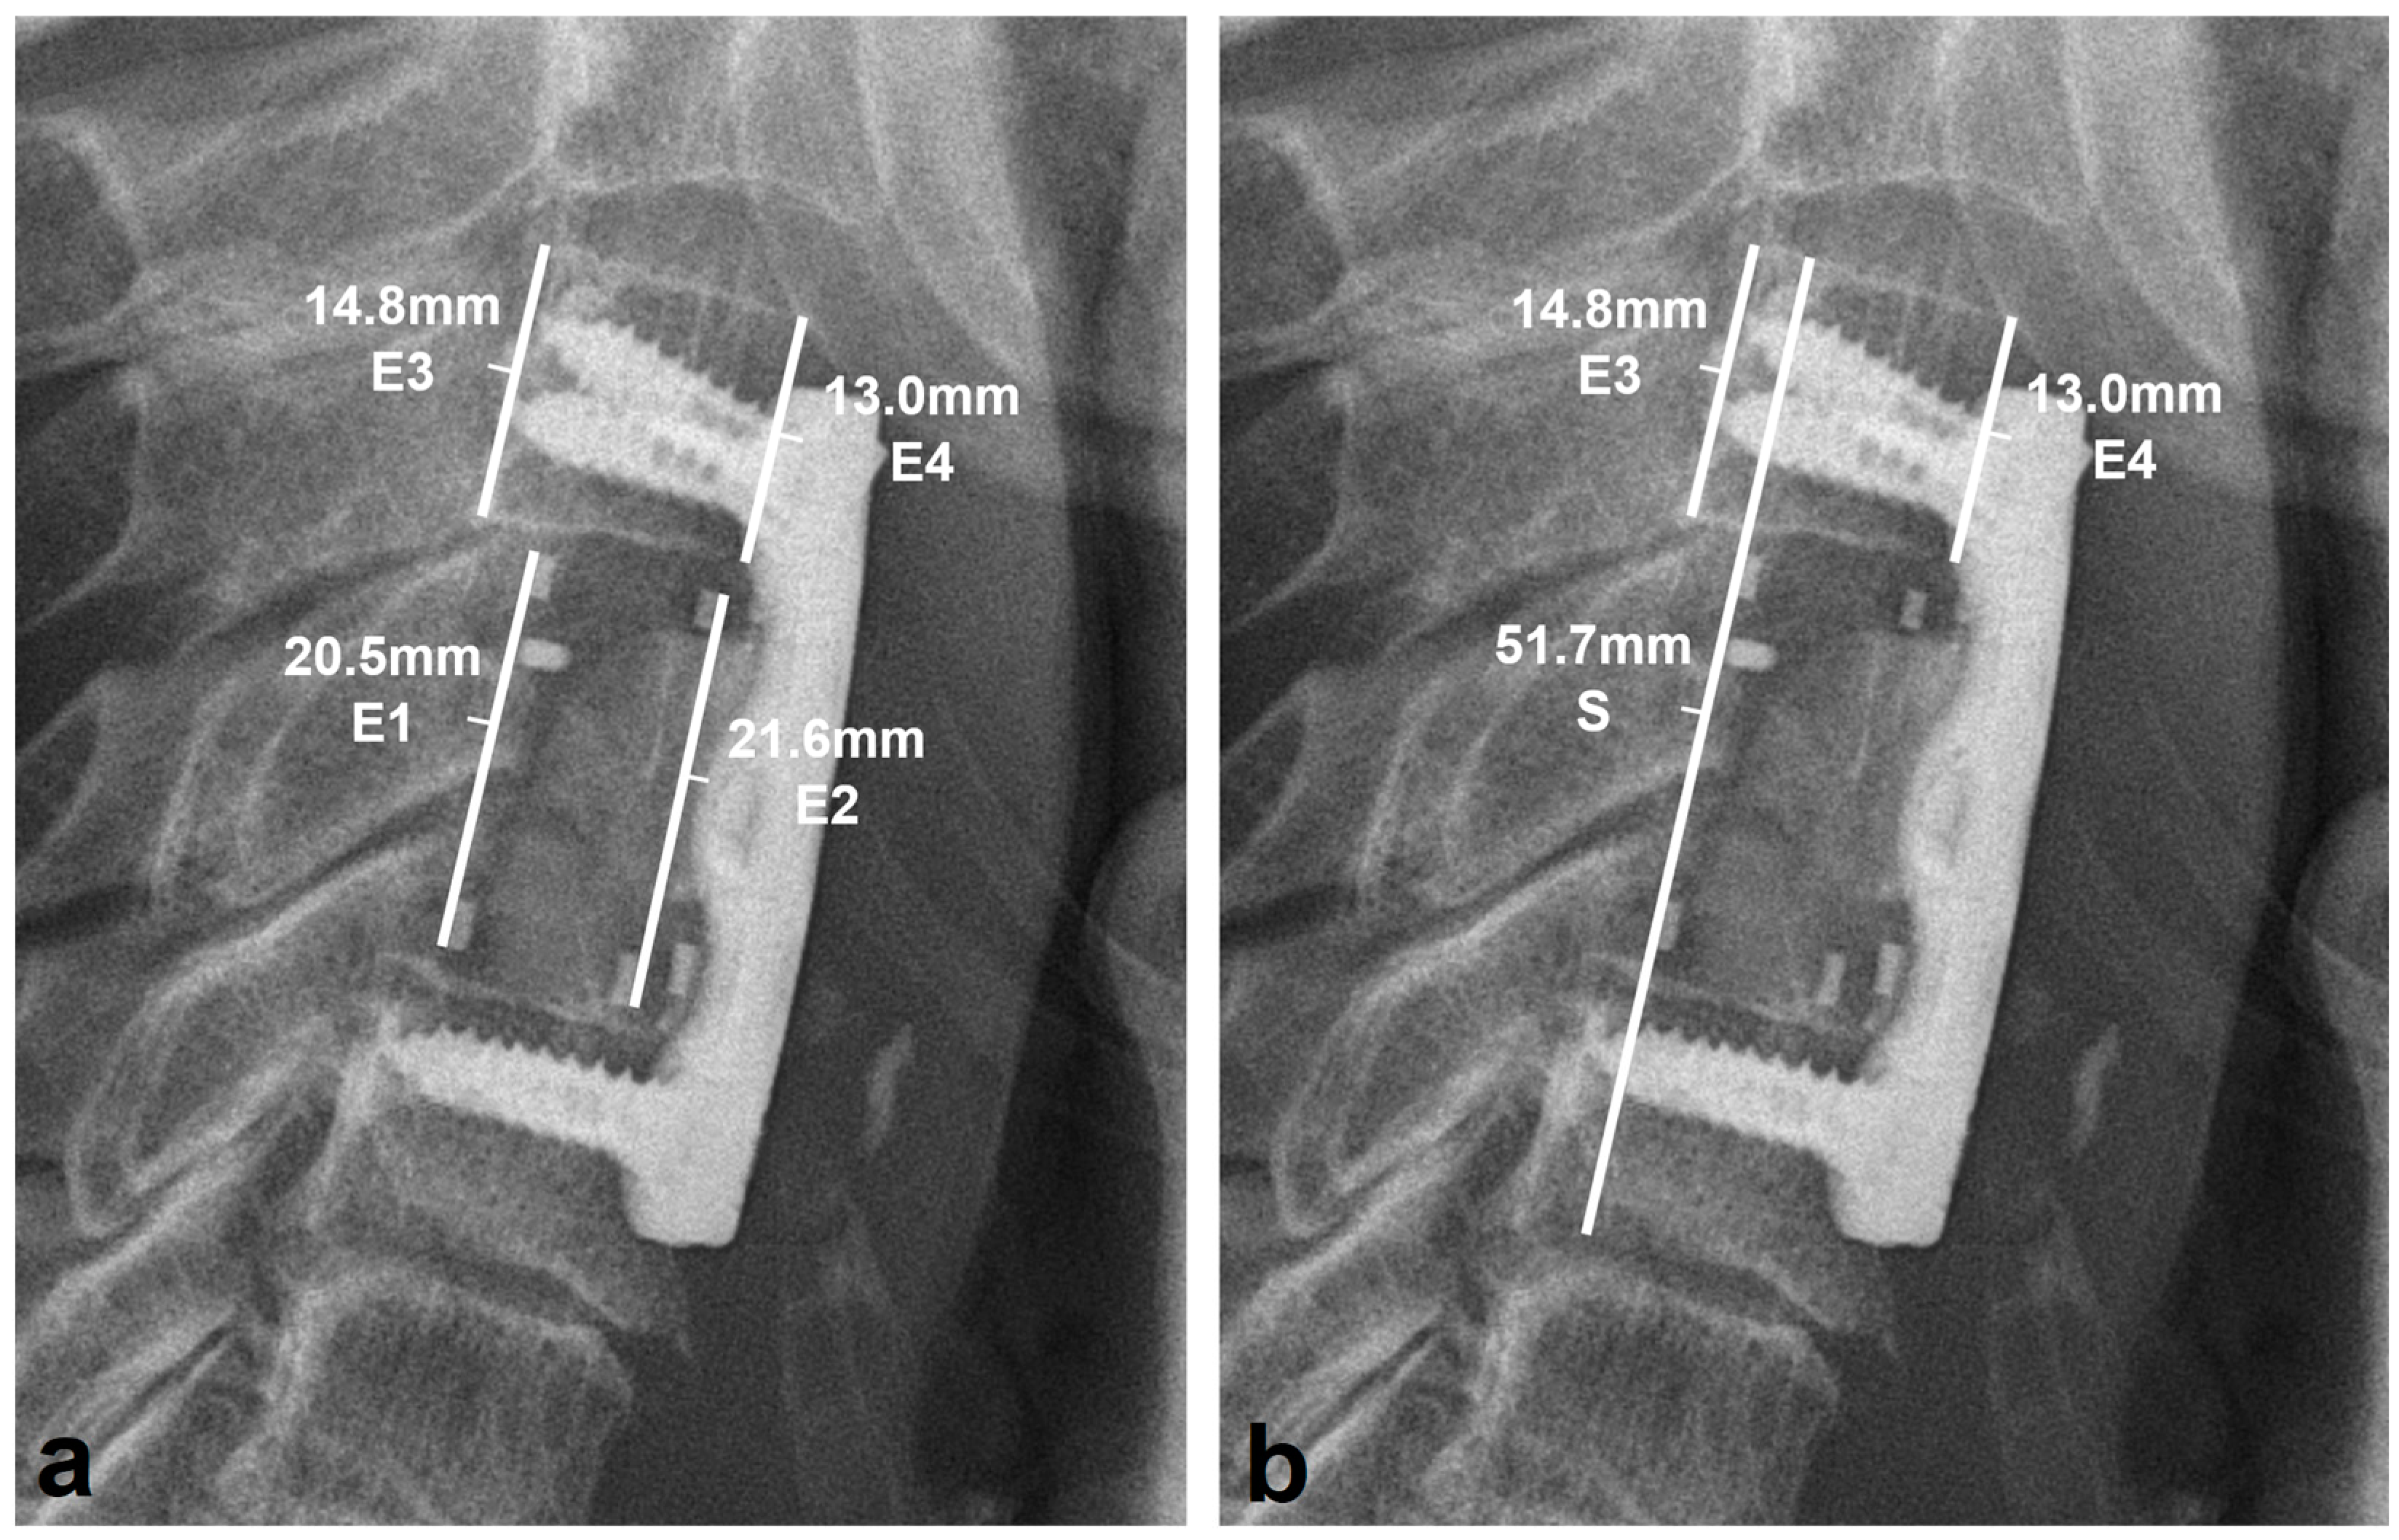

2.3. Radiologic Outcome

- Deml, M.C.; Sepulveda, C.A.M.; Albers, C.E.; Hoppe, S.; Bigdon, S.F.; Häckel, S.; Milavec, H.; Benneker, L.M. Anterior column reconstruction of the thoracolumbar spine with a new modular PEEK vertebral body replacement device: Retrospective clinical and radiologic cohort analysis of 48 cases with 1.7-years follow-up. Eur. Spine J. 2020, 29, 3194–3202. [Google Scholar] [CrossRef] [PubMed]

- Schnake, K.J.; Stavridis, S.I.; Kandziora, F. Five-year clinical and radiological results of combined anteroposterior stabilization of thoracolumbar fractures. J. Neurosurg. Spine 2014, 20, 497–504. [Google Scholar] [CrossRef] [PubMed]

- Eck, K.R.; Lenke, L.G.; Bridwell, K.H.; Gilula, L.A.; Lashgari, C.J.; Riew, K.D. Radiographic Assessment of Anterior Titanium Mesh Cages. J. Spinal Disord. 2000, 13, 501–509. [Google Scholar] [CrossRef] [PubMed]